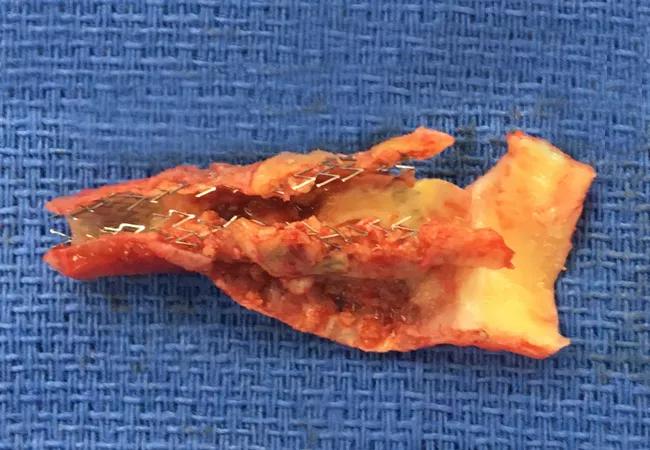

Image of Note: Resected Carotid Artery Stent

An up-close look at the result of a rare procedure

The resected atherosclerotic carotid artery stent shown above was recently removed from a patient who had undergone a carotid endarterectomy in 1994 and then had a carotid stent placed in 2004 for recurrent carotid stenosis. The earlier procedures were done at outside institutions, but the patient was referred to Cleveland Clinic’s Department of Vascular Surgery at age 63 for greater than 90 percent stenosis within her stent, attributable to atherosclerosis.

We resected her carotid artery, including the stent with atherosclerotic plaque, and did an interposition bypass. This is a complex reoperative procedure that is not commonly performed due to a significant risk of nerve injury and stroke. The patient was at particularly high risk due to significant comorbidities including diabetes, chronic kidney disease and peripheral artery disease. Despite these risks, the danger of stroke was sufficiently great to justify the procedure, and the patient has fared very well since the surgery over one month ago. She has resumed all her activities from before without any limitations. She is now scheduled for routine follow-up at six months with carotid duplex ultrasound surveillance.